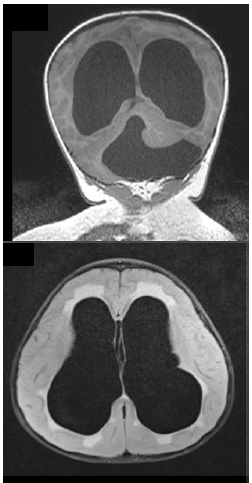

Existem diversos tipos de malformações congênitas do cérebro; muitas delas resultam em complicações motoras, sensoriais e intelectuais.

As imagens correspondem à síndrome de:

Provas